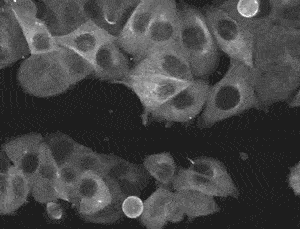

典型的黄褐斑皮疹